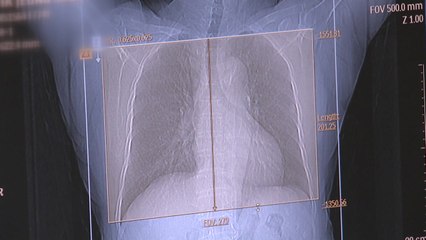

내일(7일)부터 신종코로나바이러스 감염증 의심환자에 대한 검사 대상이 확대됩니다. br br 중국이 아닌 싱가포르나 태국 등을 다녀온 경우에도 의심 증상이 있을 때, 그리고 원인 불명의 폐렴 증세가 있으면 의사의 판단에 따라 유전자 검사를 할 수 있게 됩니다. br br 한영규 기자가 보도합니다. br br [기자] br 신종코로나바이러스 검사 대상이 대폭 확대됩니다. br br 지금까지는 중국 후베이성을 방문하고 발열이나 호흡기 증상이 있는 경우, 후베이성 이외 중국 지역을 방문한 경우 폐렴 증세가 있어야 검사를 받을 수 있었습니다. br br 이 때문에 태국, 싱가포르 등을 다녀오고 신종 코로나 의심 증세가 있는 경우에도 유전자 검사를 받기가 어려웠습니다. br br 앞으로는 신종코로나바이러스가 유행하는 중국 이외 국가를 다녀온 경우나 원인을 알 수 없는 폐렴 증상이 있는 경우 의사 소견이 있으면 유전자 검사를 받을 수 있습니다. br br 6시간이면 결과가 나오는 실시간 유전자 증폭 검사도 시도 보건환경연구원뿐 아니라 50여 개 민간 의료기관으로 확대됩니다. br br 검사 대상과 검사 기관이 확대되면 신종 코로나바이러스 확진 환자가 크게 늘어날 것으로 보입니다. br br [정은경 중앙방역대책본부장 : 확진 검사를 강화하고 또 사례를 넓히다 보면 확진 환자 숫자가 더 늘어날 수도 있고 또 그렇게 조사를 하다 보면 감염원을 추정하기 어려운 그런 지역사회 감염 환자들도 발생할 수 있을 것으로 예측하고 있습니다.] br br 이럴 경우 환자를 격리해 치료할 수 있는 병상과 인력을 확보하는 게 시급합니다. br br 또한 가장 효과적인 치료제를 찾아 약을 충분히 확보하는 것도 과제입니다. br br 신종 코로나바이러스는 전염력이 매우 높은 것으로 확인된 만큼 지역사회에서의 광범위한 확산을 막기 위한 대비책 마련이 필요한 상황입니다. br br YTN 한영규입니다. br br br br ※ '당신의 제보가 뉴스가 됩니다' YTN은 여러분의 소중한 제보를 기다립니다. br [카카오톡] YTN을 검색해 채널 추가 [전화] 02-398-8585 [메일] social@ytn.co.kr [온라인 제보] www.ytn.co.krbr br ▶ 기사 원문 : ▶ 제보 안내 : , 모바일앱, social@ytn.co.